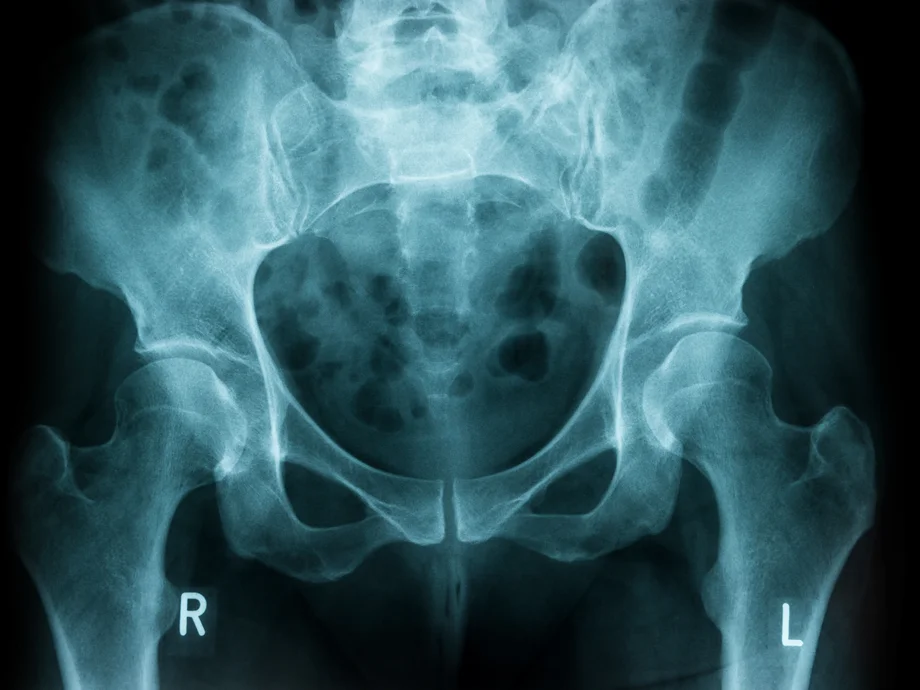

Das Leistungsspektrum unserer Klinik umfasst die Behandlung von Verletzungen, Erkrankungen und deren Folgen am Stütz- und Bewegungsapparat in jeder Altersgruppe. Als zertifiziertes Regionales Traumazentrum garantiert die Klinik eine qualitativ hochwertige Versorgung nahezu aller Unfallfolgen inklusive komplexer Becken- und Wirbelsäulenverletzungen. Patienten mit Frakturen im höheren Lebensalter werden innerhalt des zertifizierten Alterstraumazentrums im Sinne eines unfallchirurgisch-geriatrischen Co-Managements behandelt.

- Operative und konservative Knochenbruchbehandlung an oberer und unterer Extremität (Arm und Bein) einschließlich Hand, Becken und Wirbelsäule

- Fraktur-Endoprothetik der Hüfte und Schulter